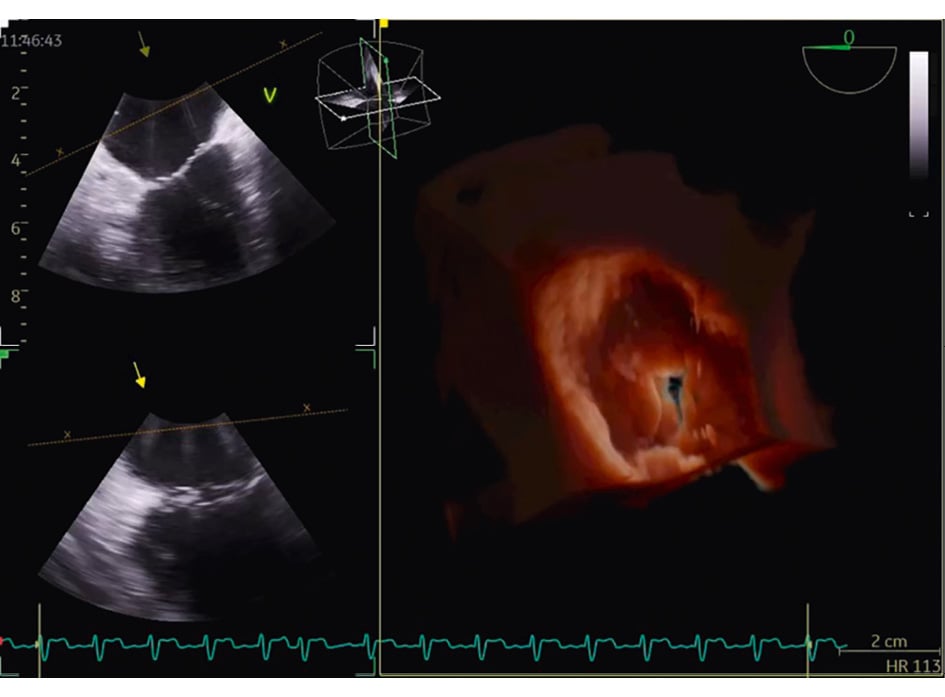

For other procedures, such as transcatheter TV repair or replacement, 3D ICE is typically complementary to TOE16. TOE is the gold standard for TV imaging, but as previously noted, the posterior positioning of the probe relative to the valve can result in far-field tangential views with acoustic shadowing from other heart structures. Given its insertion via the femoral vein and ease of positioning within the right atrium (RA), the 3D ICE probe provides enhanced visualisation of the tricuspid leaflets and annulus (Figure 1, Moving image 1). Nevertheless, it is important to note that despite these advantages, 3D ICE imaging cannot entirely replicate all TOE views, particularly the transgastric short- and long-axis views, underscoring the ongoing clinical utility of TOE in numerous scenarios17. However, this may change in the future, depending on the imaging needed for a specific TV prosthesis implant.

Figure 1. Three-dimensional reconstruction of the atrial view of the tricuspid valve.

Moving image 1. 3D reconstruction of the atrial view of the tricuspid valve.